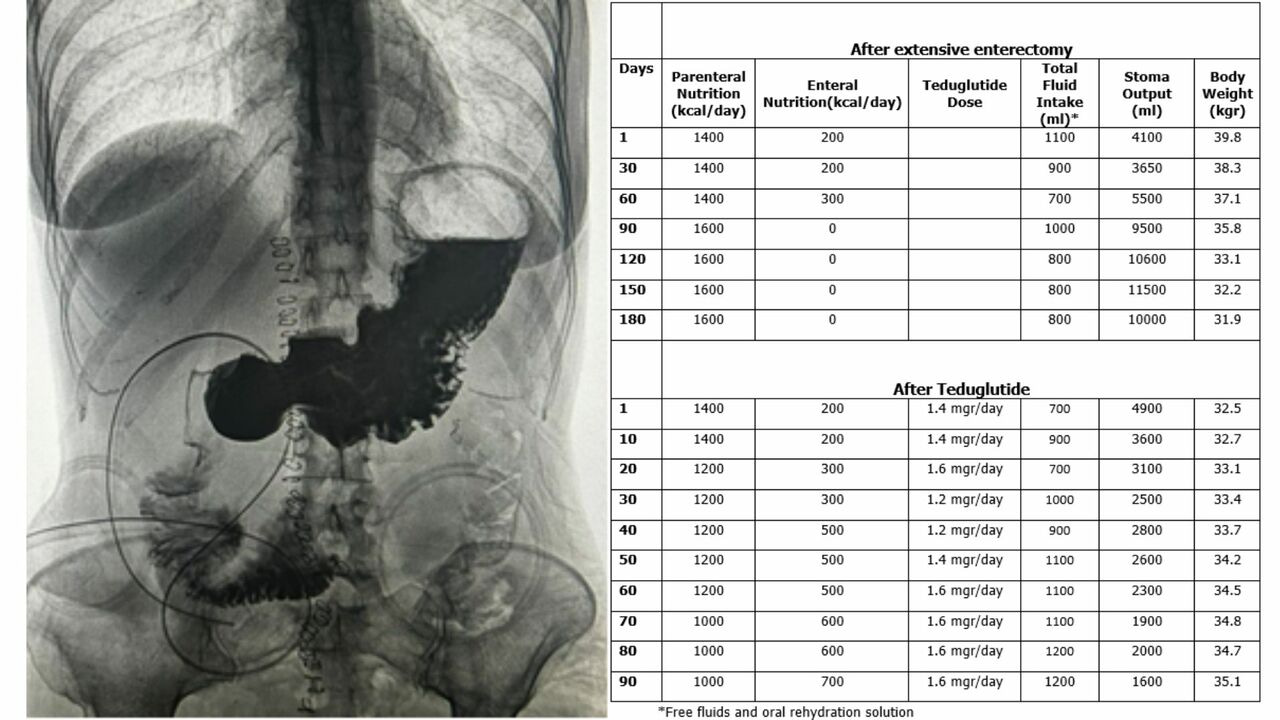

In a compelling case report, a 53-year-old female with severe malnutrition and a high-output duodenal stoma experienced a remarkable transformation with teduglutide treatment. Despite having only 5 cm of remaining small bowel, the patient's stoma output reduced from 6-12 L/day to 2.5-3 L/day within two months of teduglutide initiation. This not only stabilized electrolyte balance but also led to a notable 3-4 kg increase in body weight.

The case sheds light on teduglutide's effectiveness in managing high output stomas, even in patients with minimal small bowel. Notably, the therapy provided a breakthrough, allowing the patient to achieve energy and protein targets without compromising fluid balance. While the report acknowledges the need for further studies and consistent dosing, it underscores teduglutide's potential as a long-term treatment for SBS patients dependent on parenteral nutrition.